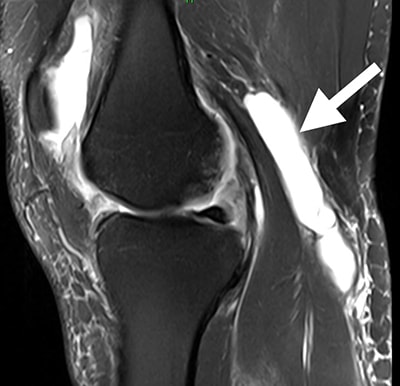

Baker's cyst

A Baker's cyst (arrow) can cause a sense of fullness behind your knee, especially when you straighten your leg.

This MRI scan shows an area of fluid behind the knee, the characteristic location of a Baker's cyst.